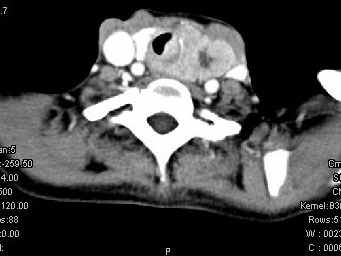

女,50岁,左下颈部扪及一质硬、表面高低不平的包块,肿块逐渐增大,现感吞咽困难,CT如图所示,最可能诊断为()

A.甲状腺癌

B.食管癌

C.喉癌

D.甲状腺原发淋巴瘤

E.颈部神经鞘瘤

[单选题]女,50岁,左下颈部扪及一质硬、表面高低不平的包块,肿块逐渐增大,现感吞咽困难,CT如图所示,最可能的诊断是()A . 甲状腺癌B . 食管癌C . 喉癌D . 甲状腺原发淋巴瘤E . 颈部神经鞘瘤